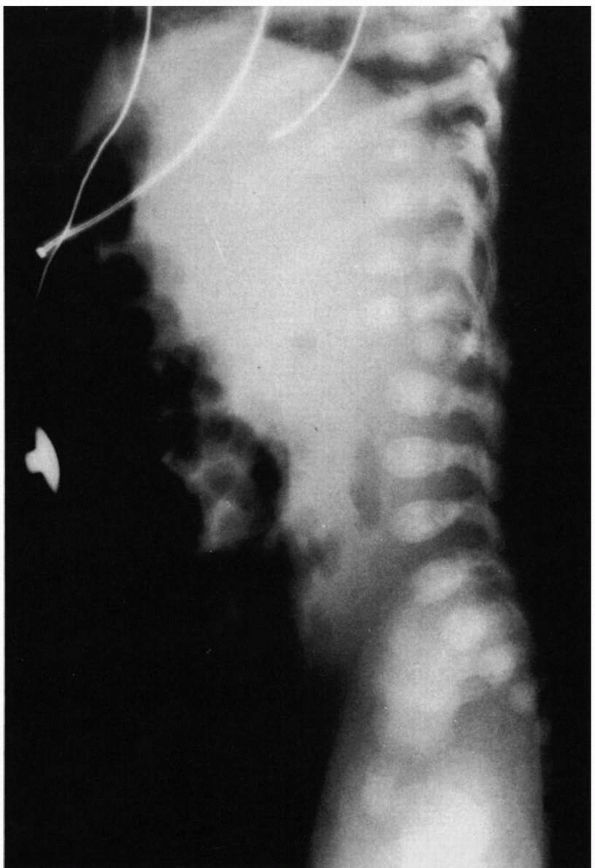

FIGURE 16-10. (A)

Thoracic curve. Ninety percent right convexity involving an average of six vertebrae: apex—T8, T9; upper end vertebrae—T5, T6; lower end vertebrae—T11, T12. (B) Lumbar curve. Seventy percent left convexity involving an average of five vertebrae: apex—L1, L2; upper end vertebrae—T11, T12; lower end vertebrae—L3, L4. (C) Thoracolumbar curve. Eighty percent right convexity involving an average of six to eight vertebrae: apex—T11, T12; upper end vertebrae—T6, T7; lower end vertebrae—L1, L2. (D) Double curve. Ninety percent right thoracic convexity and left lumbar convexity. Thoracic component, average five vertebrae: apex—T7; upper end vertebrae—T5, T6; lower end vertebrae—T10. Lumbar component, average five vertebrae: apex—T2; upper end vertebra—T11; lower end vertebra—L4. |